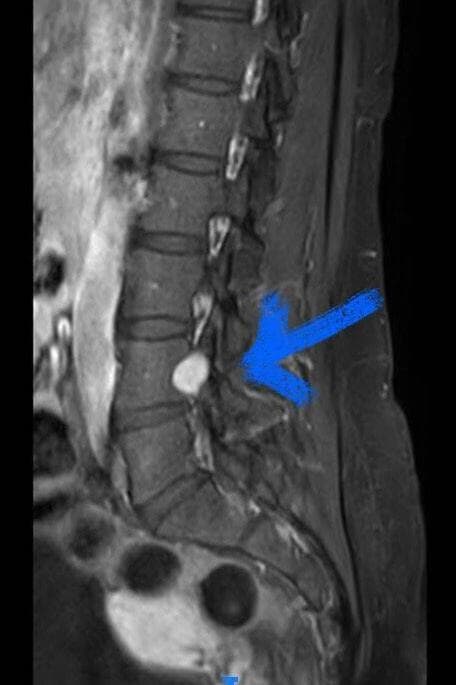

אחרי שעברה הדמיית CT אבחן נוירוכירורג את מחלתה, שוואנומה (גידול שפיר בעצב) והמליץ לה על ניתוח פתוח עם קיבוע. "חיפשתי חוות דעת שנייה ולשמחתי נאמר לי שבאיכילוב כורתים את הגידול הזה בגישה זעיר פולשנית. עם בדיקת MRI שנמסרה לרופאים נקבע לי תור לניתוח שאותו עברתי בחודש שעבר. אני עוד לא 100% אבל חזרתי לתפקוד מלא".

האבחון נעשה באמצעות סריקת MRI והטיפול כירורגי. היחידה לניתוחי עמוד שדרה באיכילוב היא בין המקומות הבודדים בעולם שמסירים גידול זה בגישה זעיר פולשנית. מסביר פרופ' לידר: "כדי להגיע למיקום השוואנומה, יש צורך להסיר את המפרק, פעולה הגורמת לחוסר יציבות בין החוליות ולצורך בקיבוע באמצעות ברגים כל זה נמנע בגישה הזעיר פולשנית".